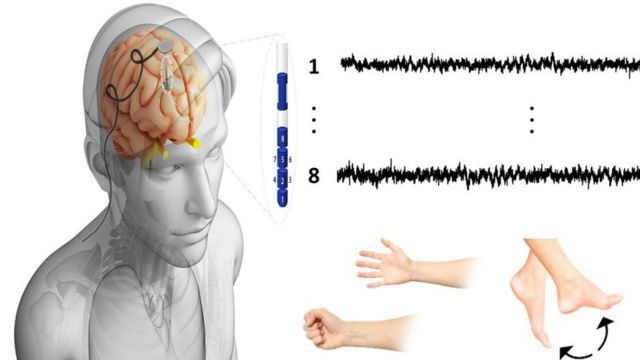

المهمة الصعبة لقراءة الدماغ البشري Bbc News عربي

أسرار الدماغ باحث أردني بجامعة أكسفورد ينشر دراسة تعطي أملا لمرضى باركنسون والإعاقات الحركية Bbc News عربي

المهمة الصعبة لقراءة الدماغ البشري Bbc News عربي